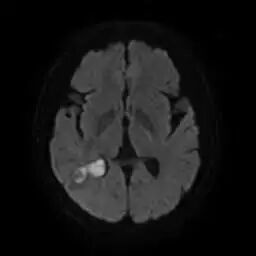

脑子里面还能进脓?很多人一听后都会非常诧异。家住普宁的陈老伯突发头痛发热随即抽搐不省人事3小时,家人急忙送到普宁市人民医院,急诊科查头颅ct提示右侧顶枕颞叶低密度影,拟抽搐查因收住我院神经内科。神经内科经完善核磁共振mr提示颅内脑脓肿可能性大,脑肿瘤待排除,请神经外科会诊后转入神经外科治疗。经黄雪钦副院长和王晓东主任医师查房讨论,结合病史和影像学检查判定陈老伯颅内的病变是脑脓肿的可能性较大。一听不是恶性肿瘤,家人喜出望外。黄雪钦副院长随后和家属进行深入的沟通,患者虽然恶性肿瘤可能性不大,但是脓肿病灶位于患者脑组织的深部,周围水肿严重,与侧脑室紧邻,一旦水肿继续加重或脓肿破入脑室,随时会有生命危险。家人听闻后陷入了深深的焦虑当中。黄雪钦副院长又耐心地向患者家属解释说,脑脓肿虽然也非常严重,但是经过积极精准的治疗预后也是非常好的。医院最近开展了神经外科机器人辅助手术,可以更加精准智能地实施微创手术清除脓肿。并详细交代了手术的获益和可能的风险,家属了解后决定行机器人辅助手术治疗。

图片

术前影像提示病灶深,紧邻侧脑室